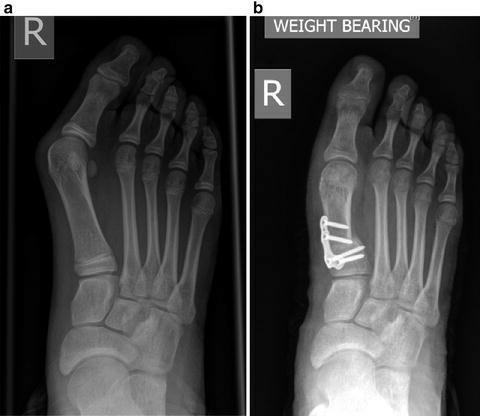

如果非手术治疗失败,可以考虑手术治疗。(证据级别:4)在选择手术前,必须确定拇外翻的严重程度。为了做到这一点,使用了负重平片射线照相术。

根据损伤的严重程度,我们可以采用以下几种外科手术:

Scarf Procedure

当畸形中等至严重时,Scarf Procedure是常用的选择。从内向外沿跖骨干纵轴截骨。将跖骨头截骨块移向外侧,并用两个螺钉固定。

Lapidus关节融合术

当观察到严重的畸形时,这是另一种选择。通过切除内侧楔形关节软骨和第一跖骨基部,两者融合。用钢板或螺钉固定。